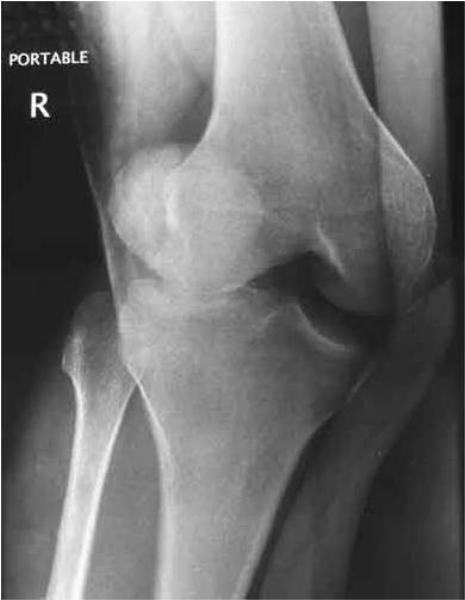

A dislocated kneecap (patella) occurs when the kneecap (patella) pops out from its normal position. This can occur as the result of trauma or it can be due to a developmental condition that leads to an improper alignment of the kneecap with the distal thighbone (femur).

The kneecap usually pops out to the outer aspect of the knee i.e. laterally.

In a normal knee, the kneecap fits nicely in the groove. But if the groove is uneven or too shallow due to developmental reasons, the kneecap could slide off, resulting in a partial or complete dislocation.

The knee looks deformed as the kneecap has gone outwards.